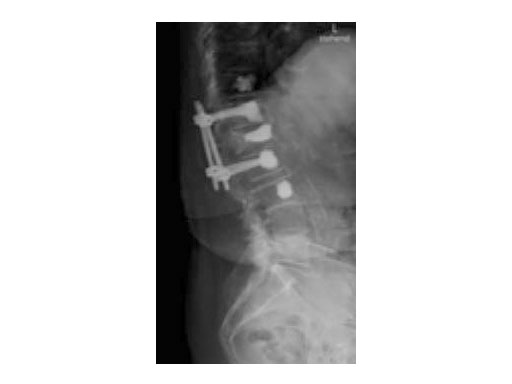

A 78-year-old woman was affected by steroid induced osteoporosis. She had persisting pain (mechanic and muscular) due to static imbalance (hyperkyphosis) and nonunion 8 months after a minor trauma with a vertebral compression fracture and vertebra plana of L1, and development of symptomatic stenosis of the spinal canal with loss of mobility over time. Pre-existing degenerative lumbar scoliosis was increased by the fracture.

Case 2: Advanced osteoporosis

A 76-year-old man was affected by advanced osteoporosis (SD -2.5) (alcohol, steroids).